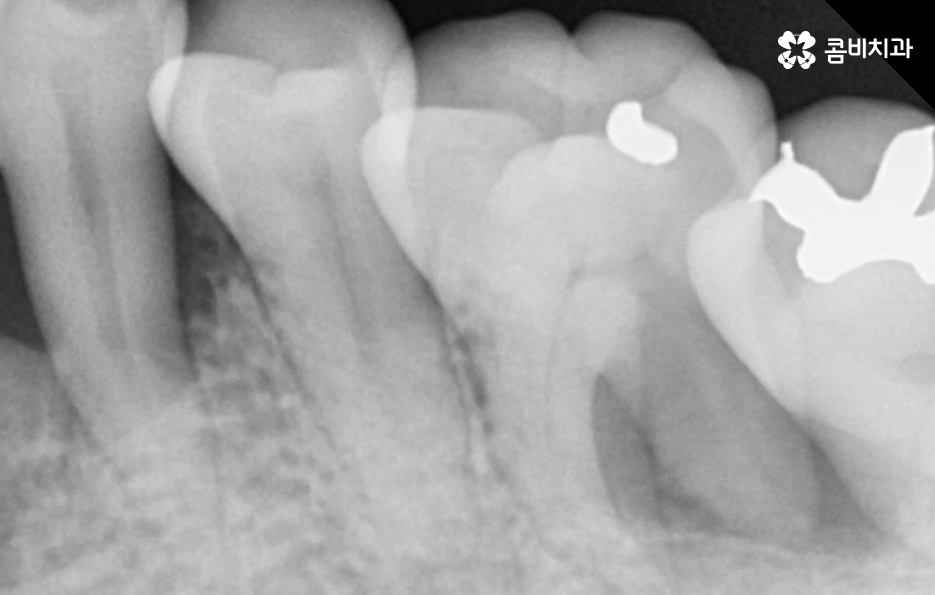

인접면 충치의 경우 치아의 씹는면에 생기는 충치보다 치료가 어려운 이유는 치아에 발생한 충치를 제거하기 위한 접근이 어렵다는 점 때문인데 치아와 치아 사이에 발생된 충치를 제거하기 위해서 다소 불필요한 치아의 삭제를 해야할 수 밖에 없고 단순히 치아의 손상 부위만을 보기 좋게 치료하는 것이 아니라 치료 후 치아의 저작력을 감안하여 치료 방법으로 고민해야 하기 때문에 지속성 측면에서 인레이 치료를 해야 하는 경우도 있어요

치아 옆면 충치의 경우 사실 더 큰 문제가 될 수 있는 점은 발견 자체가 늦어지는 경우가 많고 눈에도 잘 띄지 않기 때문에 환자분께서 검진을 미루고 다소 시리거나 아파도 참고 지내다 보면 치아의 옆부분에서 충치가 시작되었기 때문에 치아의 신경조직까지 손상되기에 쉬운 위치라는 점에서도 신경치료로 이어지는 경우도 흔하게 발생되고 있어요

우선 치아로 따지자면 치아의 씹는 면에 발생된 충치는 치료도 비교적 쉬운 편이고 치아의 구조로 볼 때도 치아의 윗 부분은 법랑질이 신경과의 거리가 어느정도 있기 때문에 충치가 몇번 치료해도 레진이나 인레이 정도로 치료가 끝낼 수 있는 경우가 많은데 치아 옆면 충치의 경우에는 치아 사이에 하루 이틀 음식물이나 이물질이 낀 것이 아니라 오랜 시간 동안 지속적으로 치실 사용이나 스케일링을 잘 안한 경우에 주로 발생되기 때문에 단순히 어금니 혹은 사랑니 주변에만 발생되는 것이 아니라 치아의 여러 부분에서 치아 옆면 충치가 동시에 발생되는 경우가 있는데요